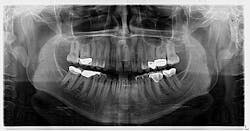

An assessment of the pan revealed two radiopaque lesions apical to the root tips of nos. 8 and 9, each measuring approximately 8 mm x 4 mm (figure 1). There was no tenderness on palpation in the generalized area. Access to a previous pan taken six years prior revealed no significant changes to the radiopacities (figure 2).

Treatment of mesiodens varies. Although typically asymptomatic, they are “often extracted for aesthetic reasons, to allow the eruption of other teeth, orthodontic reasons, and/or suspected pathology.”3 In this particular case, the mesiodentes had been stable through the years without pathology or issues with regard to the patient’s permanent dentition. We will continue to monitor the patient via regular panoramic x-rays.